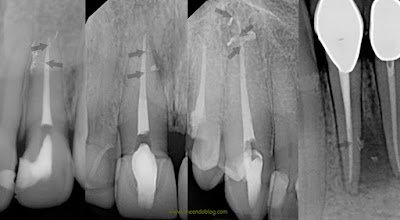

In our practice at Superstition Springs Endodontics, we have been using active irrigation for years, starting with ultrasonic and now currently using sonic activation on every case. We have found that with adequate irrigation time, sonic activation and removal of the smear layer (using EDTA), we are finding and filling more and more lateral canals, accessory canals, apical deltas. (The use of radiopaque sealers also increases the visibility) In my opinion, its difficult to say how much of this is attributed to the removal of the smear layer – but I expect that it is a combination of the active irrigation and removal of smear layer.

Here are a few of the cases demonstrating the benefits of active, sonic irrigation and smear layer removal.

So as you can see, the proper cleaning, shaping, active irrigation and removal of smear layer of the canals allows for us to open the lateral, accessory and apical deltas that we know exist in the complex canal anatomy.

Whether this changes the outcomes or success rate of the endodontic procedure is unknown, but it sure looks pretty!